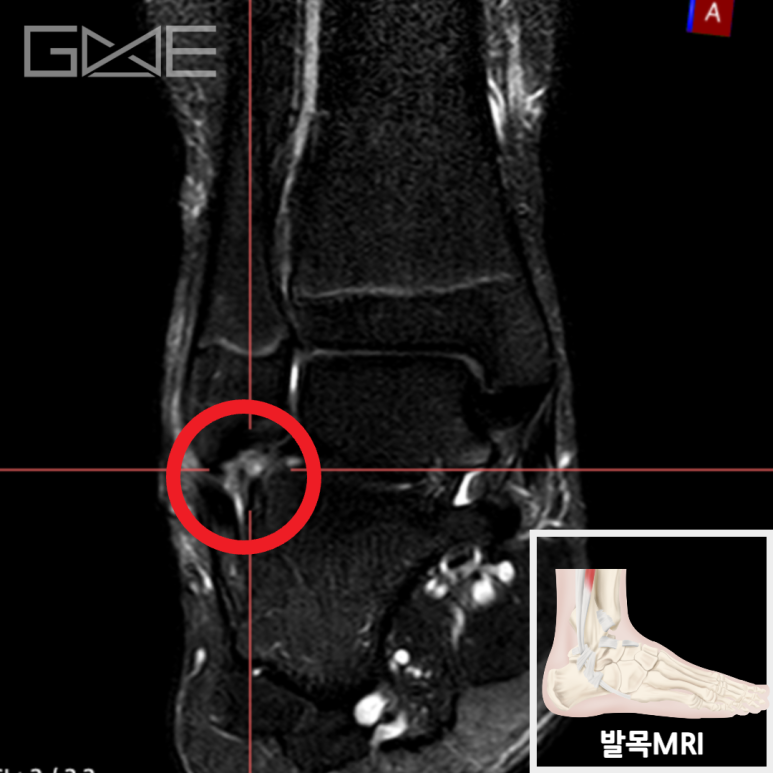

MRI상 외측 인대를 구성하는 전거비인대, 종비인대에 심한 손상이 발견되어 정형외과 병원으로 전원하였습니다.

• MRI: 외측 인대 복합체 손상 MRI: 외측 인대 복합체 손상

바깥쪽 인대를 구성하는 전거비인대, 종비인대에 심한 손상이 발견되어 정형외과 병원으로 전원